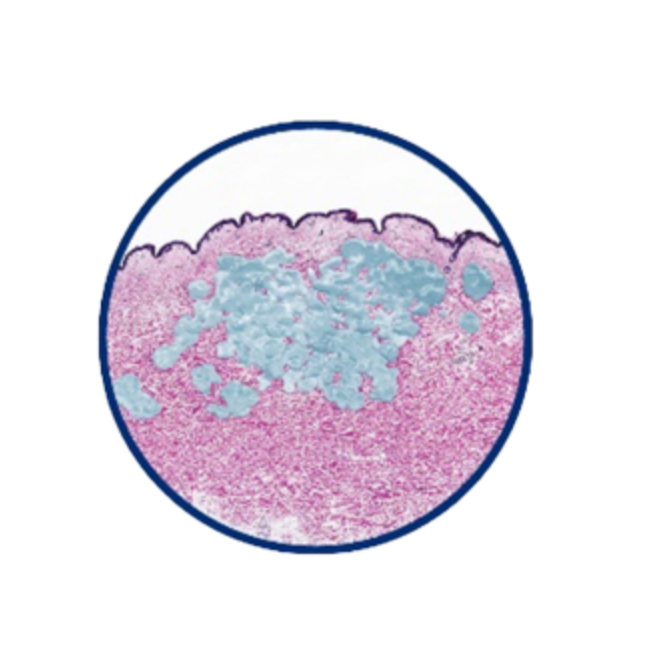

組織相容性佳 宛若天生膚感

實際切片圖

組織相容示意圖

OBT女神[動態]玻尿酸TM的微導親膚科技,讓玻尿酸膠體的質地柔韌,與肌膚緊密貼合,彷若天生膚感;同時具備良好的支撐度,強化臉部輪廓亮彩。通過美國FDA、歐盟CE與台灣衛福部核可上市,超過2,500位研究個案及全球上市後長期追蹤研究,擁有美麗同時安心。